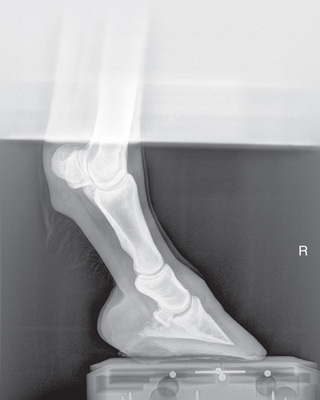

The distal phalanx and the navicular bone comprise the digit or foot. Common indications for imaging the equine foot include localized lameness by clinical examination (pain on pressure from foot testers, increased digital pulses, etc.) or by diagnostic analgesia, laminitis, penetrating wounds, or as required for a prepurchase examination.1

The three following views can be taken for the dorsoproximal-palmarodistal (DPr-PaDi) views of the foot. The terminology changes slightly depending on the actual positioning. Because the foot or the beam is at an angle to the ground, the high coronary and upright pedal routes are technically termed DPr-PaDiO views. Note that there is no lateral or medial distinction, so do not get confused.

The lateromedial view of the distal phalanx is used for all of the bones and joints of the foot.